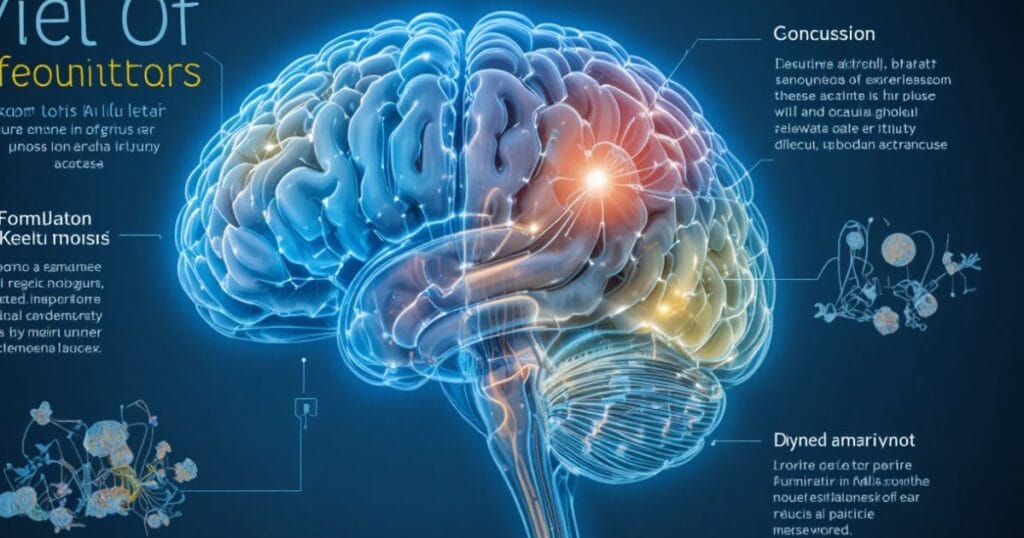

| Concussion | Sudden jolt or blow to the head causing temporary brain dysfunction. | Mild to Moderate |

| Diffuse Axonal Injury | Brain tissue tears due to rapid movement or rotation. | Severe |

Each of these injuries may require advanced brain scans after car accident such as CT or MRI to detect hidden damage.